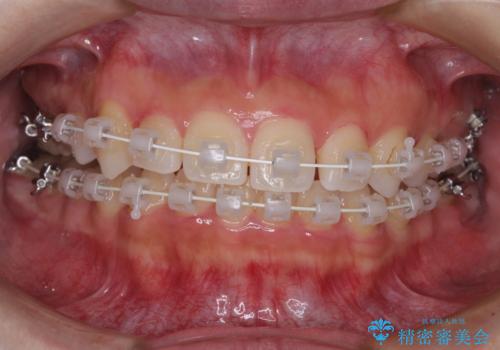

- 矯正装置

- 審美装置

- 2年7ヶ月

前から5番目の乳歯は、後続永久歯である小臼歯と比べて幅径が大きいため、移動に時間がかかりましたが、きれいに仕上げることができました。